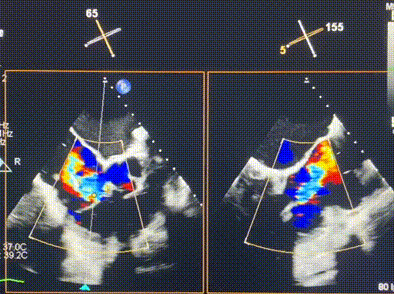

術(shù)前超聲提示重度三尖瓣反流

接受本次LuX-Valve Plus治療的是一位三尖瓣重度反流的高齡女性,患者早前曾由于二尖瓣疾病行經(jīng)導(dǎo)管二尖瓣置換術(shù),植入Tendyne瓣膜一枚,且有ICD植入史。術(shù)前CT分析結(jié)果顯示,瓣環(huán)大小為47.6mm,血管無明顯迂曲和鈣化。由于患者三尖瓣解剖結(jié)構(gòu)復(fù)雜,二尖瓣位人工瓣膜造成的超聲偽影和ICD導(dǎo)線的干擾使得歐洲沒有其他合適的商業(yè)化和臨床試驗(yàn)的產(chǎn)品可以對(duì)其進(jìn)行治療。經(jīng)過Rodrigo Estévez-Loureiro教授團(tuán)隊(duì)的詳盡術(shù)前評(píng)估,認(rèn)為LuX-Valve Plus經(jīng)導(dǎo)管三尖瓣置換系統(tǒng)可以對(duì)該患者進(jìn)行有效的治療。因此,Rodrigo Estévez-Loureiro教授團(tuán)隊(duì)最終決定使用這一中國創(chuàng)新器械為患者進(jìn)行手術(shù)。法國波爾多里爾大學(xué)附屬醫(yī)院的Thomas Modine教授與加拿大圣保羅醫(yī)院的Anson Cheung教授全程線下指導(dǎo)本次手術(shù)。